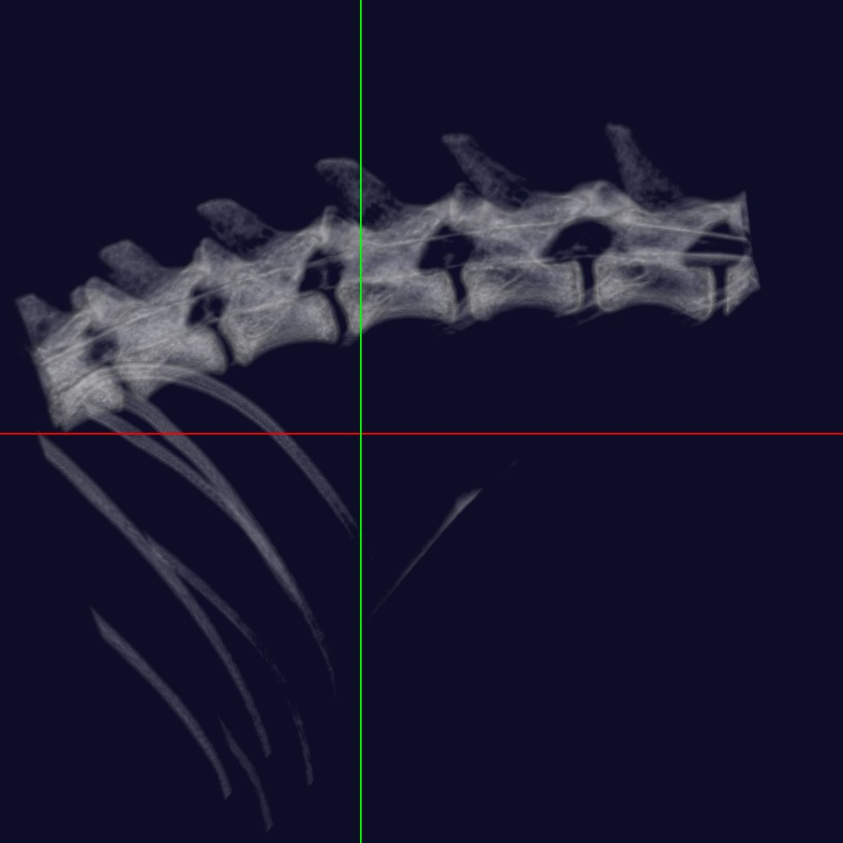

中・小型動物用3DマイクロCT

CTとはコンピューター断層撮影(Computed Tomography)の略で、X線を用いて身体の横断像(輪切り)を撮影することが出来ます。立体3D画像が得られるのも特徴で、主に骨格の異常や臓器系の異常部位、腫瘍性病変の把握に利用されます。

当院では「中・小型動物用3DマイクロCT」を導入しています。エキゾチックペットから猫・小型犬まで撮影可能です。

高画質で立体的に見ることで、レントゲンや超音波検査では分からない病態の診断や、構造が複雑な部位の細かい評価が可能です。

体の断層像に加え立体3D画像の作成が可能

事前に病変部位やその周囲の臓器との関係性を把握することで、より正確で安全な外科手術につながります。

また、飼い主様へお話しする際に、立体の3D画像のため病変のイメージがしやすくなります。

フェレット 血管造影